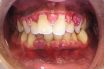

Gingivitis

Gingival inflammation. Refers to gingival inflammation induced by bacterial biofilms (also called plaque) adherent to tooth surfaces. Inflammation of the gums as a result of bacterial infection. In dentistry, an inflammation of the gingivae due to infection, impaction of food, and faulty fillings. Mild inflammation of the gums (gingiva), in which the gums become reddish,…